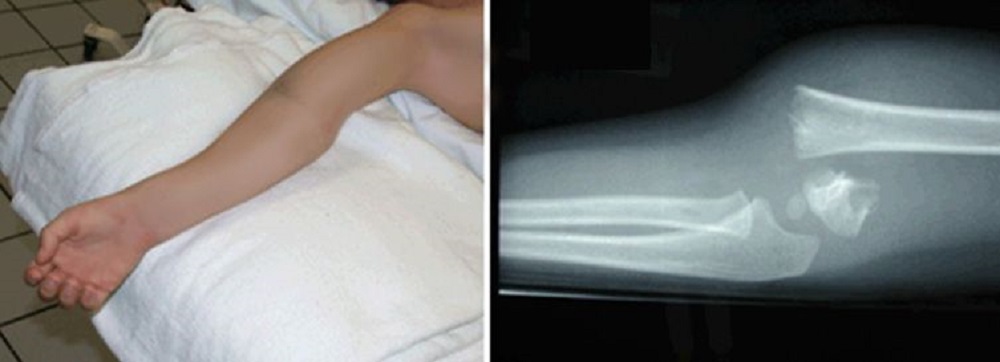

Displaced elbow fracture

(Left) This child has a severe fracture of the humerus above the elbow. (Right) This X-ray of the fracture shows that the humerus has broken into two parts — a complete displacement.

Courtesy of Texas Scottish Rite Hospital for Children